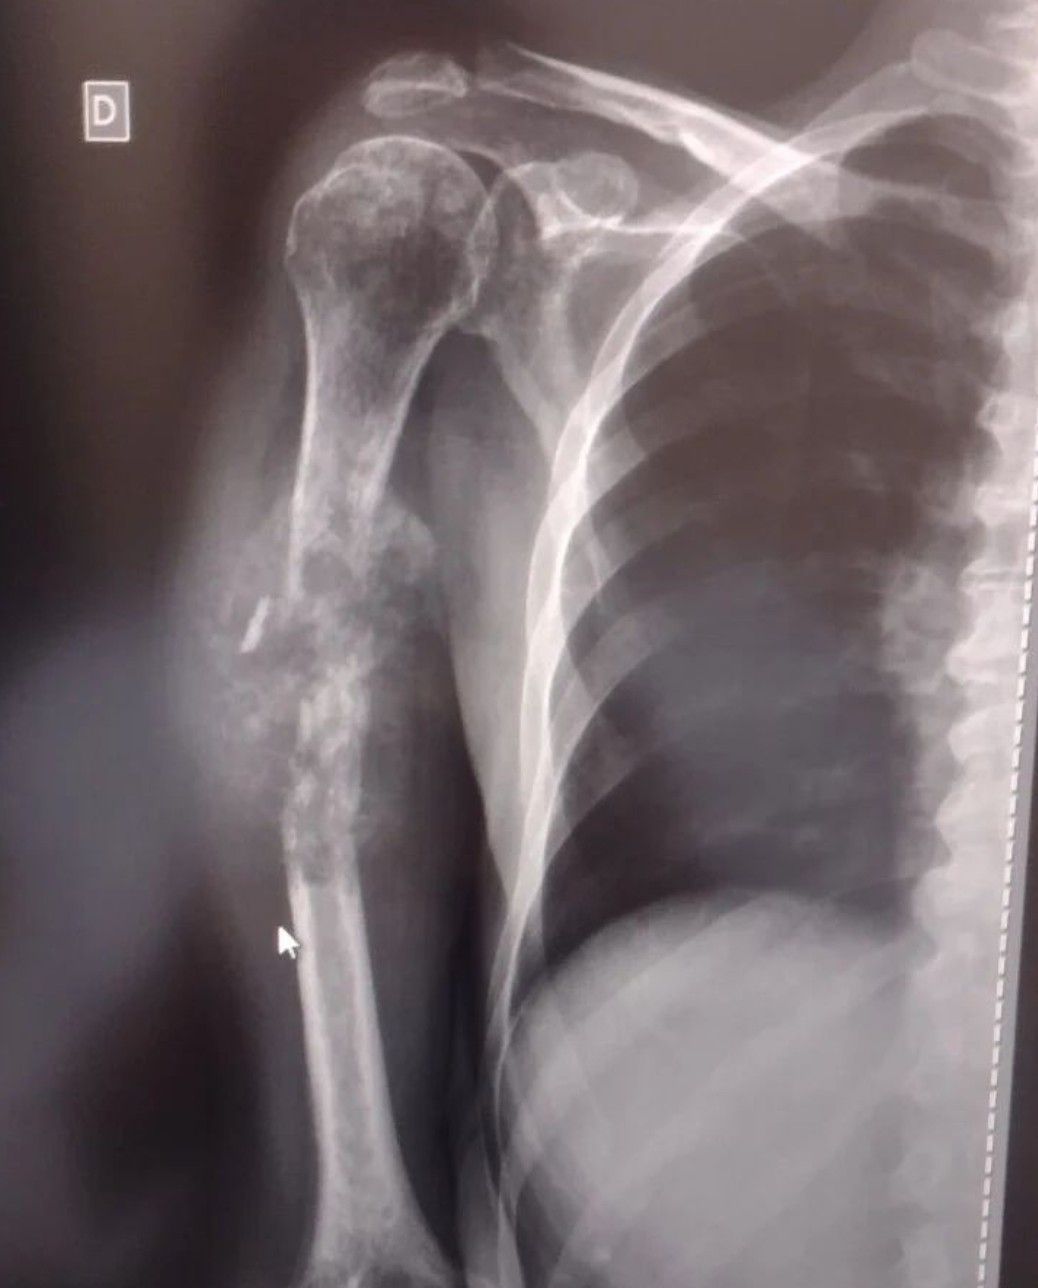

Diagnose the case with the given clinical presentation.

Comminuted bone fracture.

Ewings sarcoma

Osteosarcome